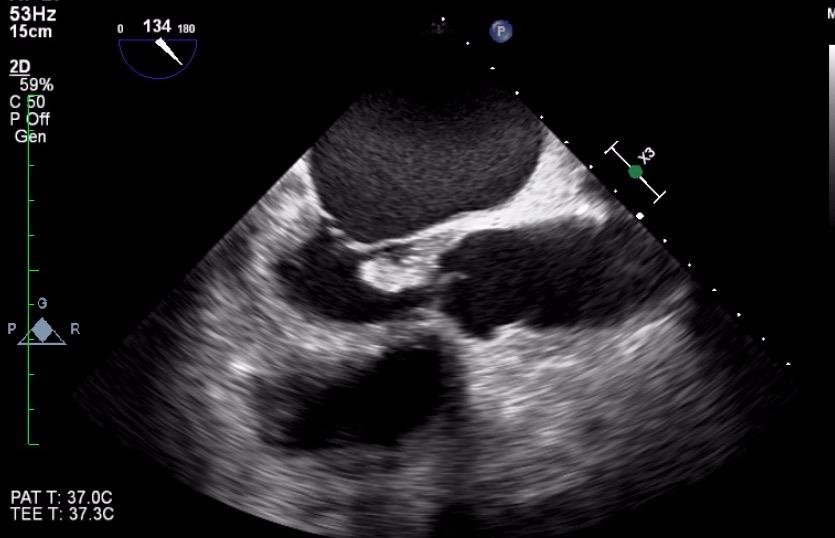

What cardiac pathology does this represent?

Aortic valve vegetations

Thickened /calcified aortic valve

Thrombus

Fibroelastoma